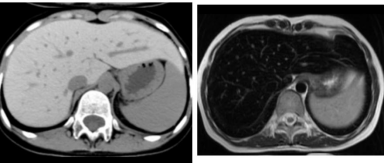

图片说明:肝脏铁过载患者,CT(左图)肝脏密度弥漫增高(白肝),MRI(右图)T2WI肝脏信号弥漫减低(黑肝)

正常肝脏的CT值通常在50-70HU之间,而铁过载时肝脏CT值可升高至80HU以上,重度铁过载甚至可达100HU以上,明显高于脾脏(正常脾脏CT值约40-50HU),形成“肝脾密度倒置”的特征性表现。这种高密度改变呈弥漫性分布,累及整个肝脏,不会出现局灶性低密度区,可与脂肪肝(肝脏CT值降低)、肝硬化(结节样密度不均)等疾病鉴别。

MRI对铁过载的敏感性远高于CT,其核心机制在于铁的顺磁性特性。过量的铁离子会缩短肝脏组织的T2弛豫时间,导致在T2加权像(T2WI)上信号显著降低,肝脏表现为弥漫性“发黑”,即“MRI黑肝”。

在不同MRI序列中,铁过载的表现存在差异:T1加权像(T1WI)上肝脏信号变化通常不明显,难以发现轻度铁过载;而T2WI尤其是脂肪抑制序列,肝脏信号降低的特征最为突出,轻度铁过载即可表现为信号轻度变暗,重度铁过载时肝脏信号甚至接近无信号的骨骼或气体。此外,T2*WI对铁的敏感性更高,能检测出极少量的铁沉积,是目前诊断早期肝脏铁过载的首选序列。